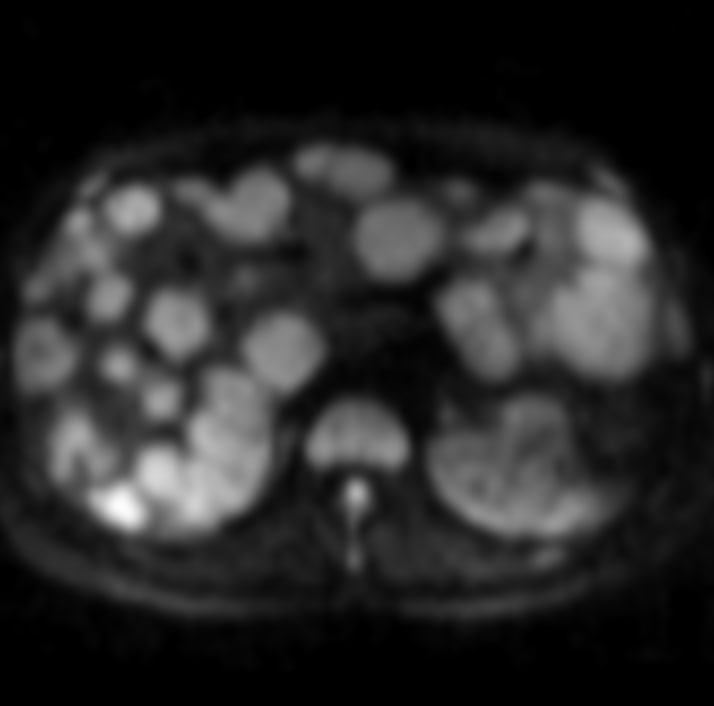

40 лет.

Думаю, что рак в хвосте панкреас, с вот такими метастазами в печень.

Ну, или и в панкреас тоже метастаз, хотя, других опухолей в животе не обнаруживается.